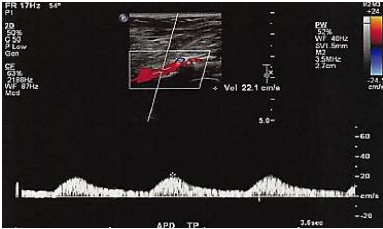

A imagem a seguir representa análise da artéria poplítea.

Assinale a alternativa que apresenta qual padrão de onda representado.